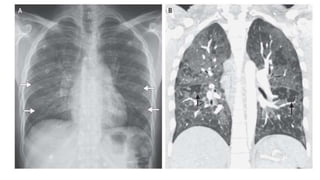

• Rx de tórax: infiltrado intersticial difuso con un patrón que inicia en las regiones

parahiliares y progresa a las zonas apicales y periféricas. En el 20% de los casos

se pueden encontrar lesiones quísticas y neumotórax; rx normal en 30%.

• TAC de torax: presencia de opacidades en vidrio deslustrado y/o lesiones

quísticas